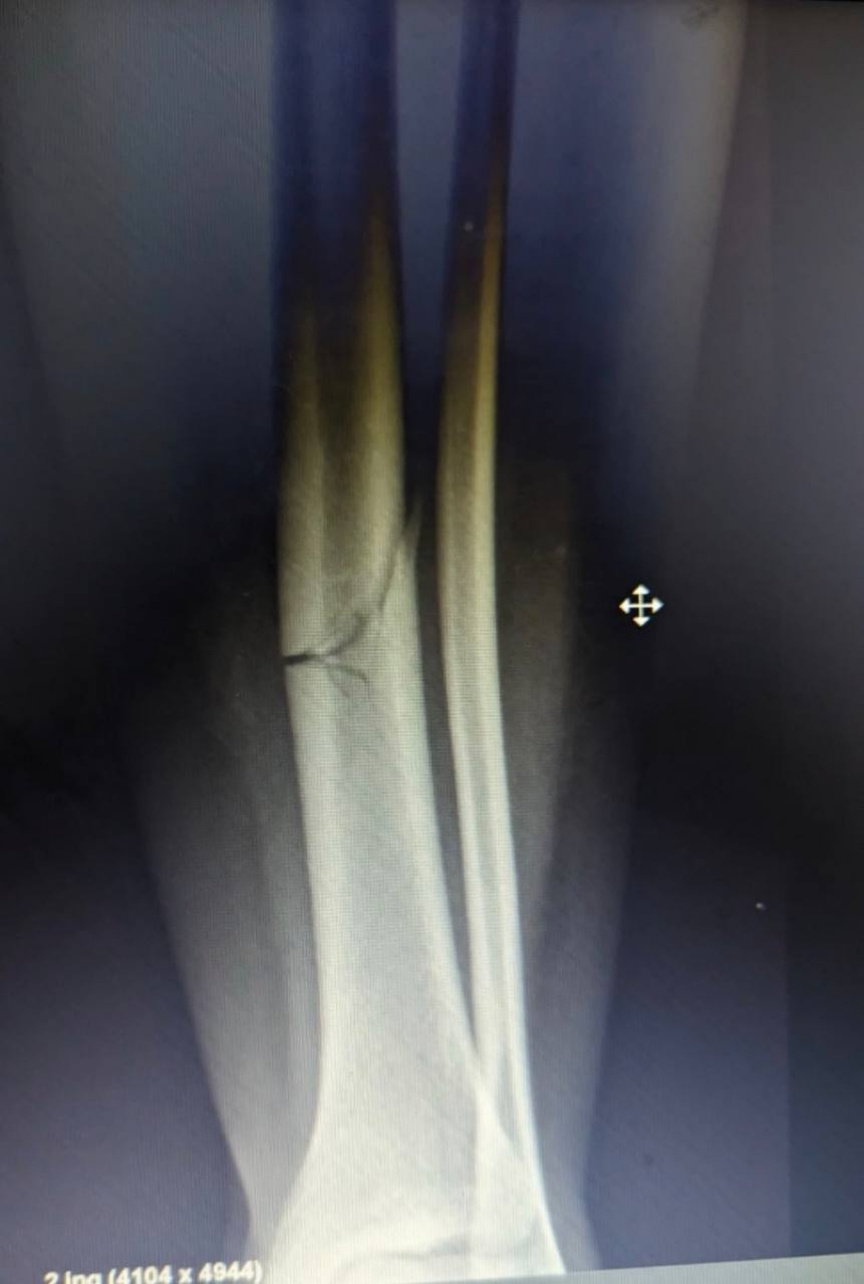

މީގެ އިތުރުން، އޭނާގެ ފައި ބިންދައިގެން ގޮސްފައި ވާކަމަށާއި އެކަމަށް ވެސް އެކަށީގެންވާ ފަރުވާ ނުލިބޭކަން އޭނާ ފާހަގަ ކުރިއެވެ. އަދި ގއ. އަތޮޅު ހޮސްޕިޓަލުގައި ކަށީގެ ޑޮކްޓަރެއް ނެތުމުން މަސައްކަތްކުރީ ގދ. ތިނަދޫއަށް ފޮނުވަން ކަމަށާއި ނަމަވެސް ތިނަދޫން ވެސް އޮޕަރޭޝަން ކުރެވެން ނެތްކަން އޭނާ ފާހަގަކުރިއެވެ.

އެކްސިޑެންޓުގައި އަނިޔާވި އަންހެން މީހާއަށް ލިބިފައިވާ އަނިޔާތައް

އެތައް އިރަކަށް ފަހު، އިތުރު ގޮތެއް ނެތިގެން ފައިގައި ޕްލާސްޓަރު އެޅިއިރު، ޕްލާސްޓަރު ވެސް ފުރަތަމަ އެޅީ ނުބައިކޮށް ކަމަަށް އޭނާ ބުންޏެވެ.